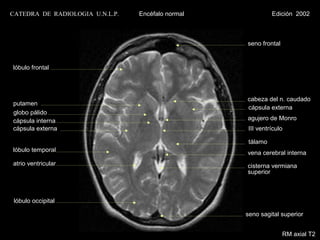

CATEDRA DE RADIOLOGIA U.N.L.P.   Encéfalo normal             Edición 2002

seno frontal

lóbulo frontal

cabeza del n. caudado

putamen

cápsula externa

globo pálido

cápsula interna                                    agujero de Monro

cápsula externa                                     III ventrículo

tálamo

lóbulo temporal                                    vena cerebral interna

atrio ventricular                                  cisterna vermiana

superior

lóbulo occipital

seno sagital superior

RM axial T2